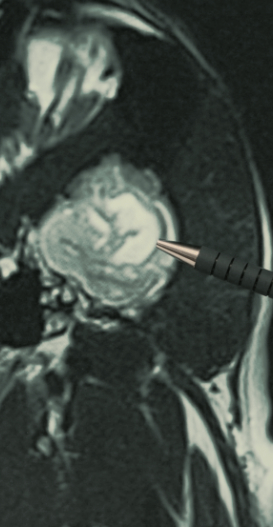

Obraz RM mózgu psa

Badania z podaniem kontrastu, zwiększające szczegółowość obrazowania.